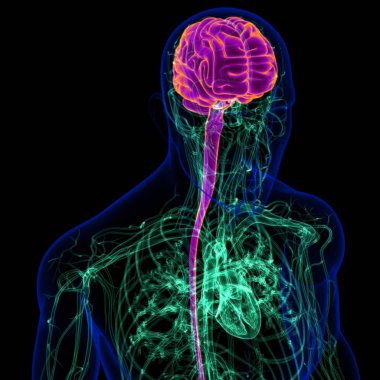

Tıbbi Konsept için sinir sistemi anatomisi olan 3D İnsan Beyni

MaviGrafikselresimlemeŞeffafİnsanSağlıkBaşıİlaçerkekkordonüç boyutlubiyolojikHücregövdeHastalıkİstihbaratİçeridebiyolojiBilimSistemAcıorgzihinomurgaelektronİşaretgörüntü oluşturmaanatomiomurilikbeyinMerkezGerginNörolojimikroskobikBeyin fırtınasıSıhhiyeanatomikSinirbeyincikcerebra3d oluşturmaüzerine siyahsinir hücresiBenzer İçerikler